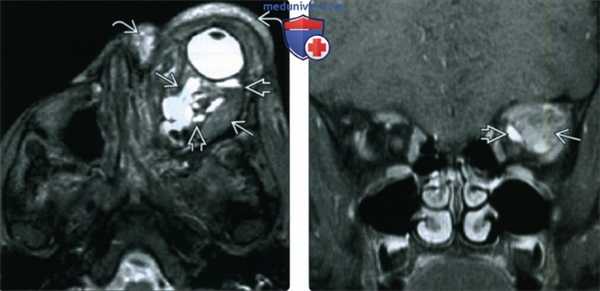

(Справа) При Т1-взвешенной МРТ в аксиальной проекции определяется инфильтративное образование, распространяющееся на несколько смежных пространств. В задней части образования, лежащей в пределах мышечного конуса, в просвете макрокистозных полостей видны уровни жидкость-жидкость. Пресептальный и передний внутриглазничный компоненты выглядят более гомогенными и гипоинтенсивными, что указывает на их микрокистозное строение или наличие венозных элементов. (Слева) У ребенка отмечено резкое усиление длительно существовавшего правостороннего экзофтальма. При Т2-взвешенной МРТ в аксиальной проекции определяется крупное дольчатое ретробульбарное объемное образование с характерными уровнями «жидкость-жидкость». Различная высота уровней жидкости указывает на многокамерное строение образования.

(Справа) На Т1-взвешенной постконтрастной аксиальной томограмме у этого же пациента отмечается вариабельность сигнала содержимого и те же уровни жидкость-жидкость, указывающие на белковое и геморрагическое содержимое. В задней части образования отмечается легкое контрастирование венозного компонента.

(Слева) При Т2-взвешенной МРТ в аксиальной проекции определяется массивная лимфатическая мальформация сложной формы, вызывающая экзофтальм. Жидкое содержимое, скопившееся в результате неоднократных кровоизлияний, дает вариабельный сигнал и формирует уровни раздела. Также виден еще один, пресептальный, компонент образования.

(Справа) При МРТ Т1ВИ FS с КУ в левой глазнице определяется крупное образование сложной формы, содержащее по большей части неконтрастируемый субстрат, дающий вариабельный Т1-сигнал. Контрастируемая структура с медиальной стороны представляет собой венозный компонента, вероятно, мелкий варикозный узел.

(Слева) При аксиальной Т1ВИ С+ FS у ребенка старшего возраста с обострением хронического правостороннего проптоза, обусловленного геморрагической лимфатической мальформацией глазницы, определяется жидкость белковою и геморрагического характера; видны уровни «жидкость-жидкость» на границе раздела сред.

(Справа) При аксиальной MPT Т2 FS у этого же пациента за глазным яблоком визуализируется крупное объемное образование с характерными уровнями «жидкость-жидкость». Различная высота уровней позволяет сделать заключение о многокамерном объемном образовании глазницы.